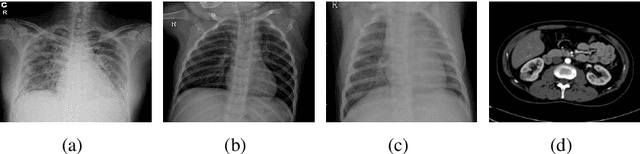

Abstract:Over the years, the paradigm of medical image analysis has shifted from manual expertise to automated systems, often using deep learning (DL) systems. The performance of deep learning algorithms is highly dependent on data quality. Particularly for the medical domain, it is an important aspect as medical data is very sensitive to quality and poor quality can lead to misdiagnosis. To improve the diagnostic performance, research has been done both in complex DL architectures and in improving data quality using dataset dependent static hyperparameters. However, the performance is still constrained due to data quality and overfitting of hyperparameters to a specific dataset. To overcome these issues, this paper proposes random data augmentation based enhancement. The main objective is to develop a generalized, data-independent and computationally efficient enhancement approach to improve medical data quality for DL. The quality is enhanced by improving the brightness and contrast of images. In contrast to the existing methods, our method generates enhancement hyperparameters randomly within a defined range, which makes it robust and prevents overfitting to a specific dataset. To evaluate the generalization of the proposed method, we use four medical datasets and compare its performance with state-of-the-art methods for both classification and segmentation tasks. For grayscale imagery, experiments have been performed with: COVID-19 chest X-ray, KiTS19, and for RGB imagery with: LC25000 datasets. Experimental results demonstrate that with the proposed enhancement methodology, DL architectures outperform other existing methods. Our code is publicly available at: https://github.com/aleemsidra/Augmentation-Based-Generalized-Enhancement